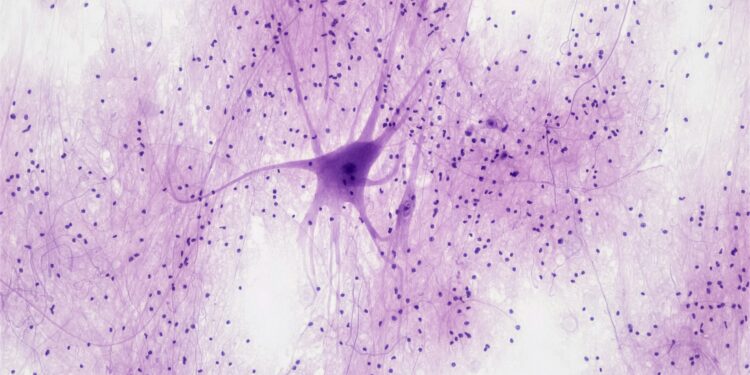

The disease is caused by mutations in specific genes that result in harmful protein clumping within brain cells. These clumps disrupt brain function and lead to neuronal death. In an effort to develop a treatment, researchers are exploring the use of “peptide-brush polymers.” These peptides are naturally occurring proteins that can potentially prevent the damaging clumping of proteins associated with Huntington’s disease.

In mouse studies, this polymer-based treatment showed promising results by “rescued” damaged brain cells and even reversing some of the symptoms of Huntington’s disease. The research team, including scientists from Northwestern University and Case Western Reserve University, observed significant improvements in brain health and behavior in the treated mice, though they cautioned that results in mice do not always translate to humans.

The polymer developed by Gianneschi’s lab allowed the peptide to cross the blood-brain barrier and target the affected brain cells. In mouse experiments, the polymer successfully entered the brain and prevented mitochondrial damage—protecting the brain cells. The treated mice exhibited more normal behavior, such as exploring their environment, which they had previously avoided due to the effects of the disease. The polymer treatment also showed no signs of toxicity, an encouraging sign for future human trials.